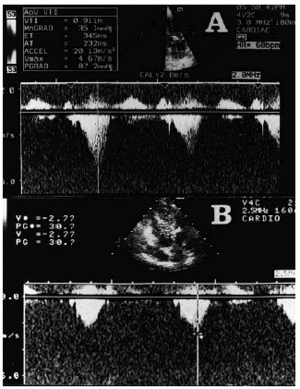

En noviembre de 1998 ingresa por deterioro de clase funcional (IV NYHA), ortopnea, aumento del perímetro abdominal, oliguria y edemas generalizados, con una ganancia ponderal de 10 kg en los últimos 3 meses. En la exploración física, la presión arterial era de 130/70 mmHg, la presión venosa yugular estaba elevada; se auscultaban crepitantes en ambas bases pulmonares y un soplo sistólico 3/6 en borde esternal izquierdo y foco aórtico, no irradiado a carótidas, que aumentaba con la maniobra deValsalva. El electrocardiograma evidenciaba ritmo sinusal de 70 lat/min, criterios de voltaje de crecimiento de aurícula izquierda y de ventrículo izquierdo, con alteraciones secundarias de la repolarización (descenso del segmento ST de 1 mm con onda T negativa en I, aVL, V5 y V6). En la radiografía de tórax se observaba cardiomegalia y redistribución vascular. La analítica en el ingreso presentaba anemia crónica (hemoglobina 10,2 g/dl), creatinina 1,7 mg/dl (su valor era de 1,5 mg/dl de manera estable tras el trasplante renal en 1996), con sedimento de orina normal. Se realizó un ecocardiograma que puso de manifiesto hipertrofia asimétrica del ventrículo izquierdo, con fracción de eyección del 80% y un patrón de relajación alterado con una relación E/A de 0,6. Se detectó la existencia de un gradiente subaórtico máximo de 87 mmHg (fig. 1a) que aumenta hasta 111 mmHg con la maniobra de Valsalva. Además, presentaba movimiento anterior sistólico (SAM) de la válvula mitral e insuficiencia mitral moderada. Durante los primeros días de ingreso se realizaron balances hídricos negativos con disminución de los edemas y pérdida de 4 kg de peso. Sin embargo, la paciente presentó posteriormente un deterioro progresivo de la función renal hasta alcanzar una cifra de creatinina de 3,4 mg/dl, con nueva ganancia ponderal y oligoanuria, a pesar de intensificar tratamiento diurético, motivando su ingreso en la unidad coronaria y la necesidad de ultrafiltración. El balance hídrico negativo previsto para las sesiones de ultrafiltración era 2.000 ml. Cuando el volumen extraído era entre 150 ml y 400 ml (no había transcurrido una hora desde el inicio de las sesiones) la paciente presentaba reiteradamente cuadros de hipotensión (la presión arterial sistólica caía a 60-80 mmHg) y disnea, con desaturación arterial (88-90%, pulsioximetría), obligando a suspender las sesiones de ultrafiltración. La PVC disminuía entre 2 y 5 mmHg previamente a los cuadros de hipotensión. Estos episodios de bajo gasto, atribuídos al empeoramiento de la obstrucción subaórtica por la disminución de la precarga, respondían rápidamente a la administración de expansores del plasma (entre 100 y 250 ml de Elohes®) y propranolol intravenoso (entre 5 y 15 mg). Finalmente, ante la mala evolución de la paciente, la gran dificultad para el tratamiento de la volemia y la existencia de una miocardiopatía hipertrófica obstructiva refractaria al tratamiento convencional, se decidió implantar un marcapasos bicameral DDD-R, programándose de manera empírica un intervalo PR de 120 ms. Tras la estimulación secuencial AV se logra reducir el gradiente subaórtico a 30 mmHg (fig. 1b), con desaparición del SAM y la insuficiencia mitral, y se consiguió una adecuada tolerancia de las sesiones de ultrafiltración. Precisó ultrafiltración durante 5 días tras el implante del marcapasos y toleró extracciones de 2.000 ml (en 4 h) cada día. La evolución posterior de la paciente fue satisfactoria, con recuperación de su función renal basal y desaparición de los edemas.

Fig. 1. Gradiente subaórtico valorado por ecocardiografía Doppler. (a) Gradiente basal de 87 mmHg; (b) el gradiente disminuye a 30 mmHg tras implantar marcapasos DDD-R.